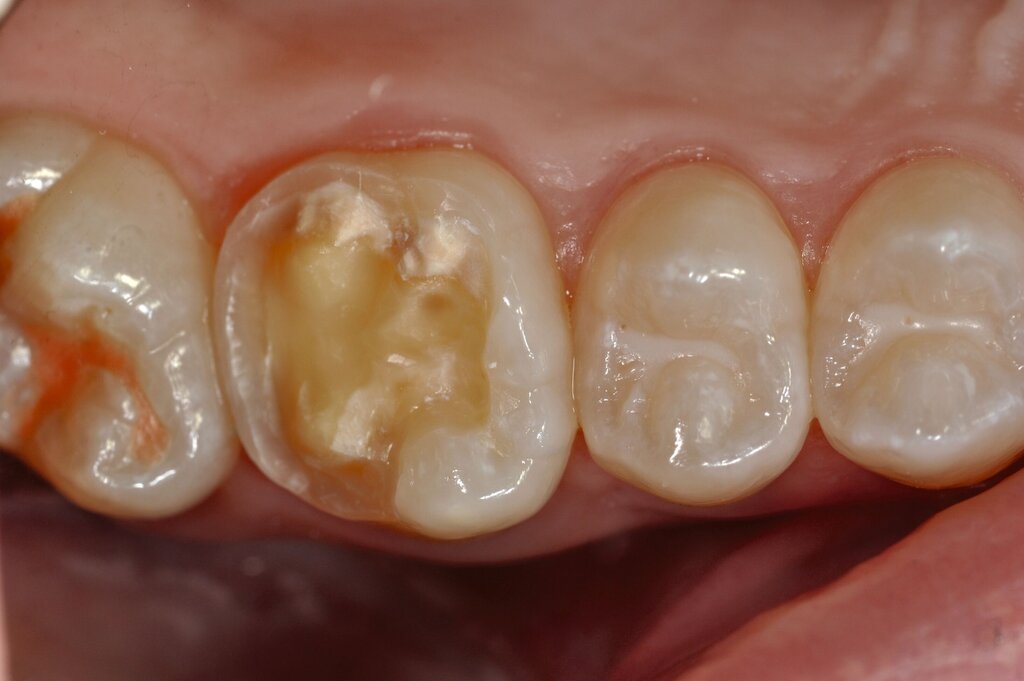

Die temporäre Therapie C (kurzfristig)

Die Therapie C hat das Ziel, MIH-Zähne vorübergehend zu versorgen, bis der vollständige Durchbruch der Zähne eine adhäsive Restauration ermöglicht, um die hypersensiblen Zähne zu desensibilisieren oder/und die Mitarbeit für die weitere Behandlung aufzubauen. Vor dem Hintergrund des erhöhten Kariesrisikos dieser Zähne (Abbildung 2) muss durch die Maßnahmen eine Kariesprogression vermieden werden.

Die direkte Versorgung mit Komposit hat den Vorteil, dass durch die Verwendung von Dentinadhäsiven das Dentin dicht versiegelt werden kann. Hypersensitivitäten werden dadurch deutlich reduziert. Zudem kann der Zahn bei der direkten Versorgung sehr defektorientiert versorgt werden (Abbildung 7).